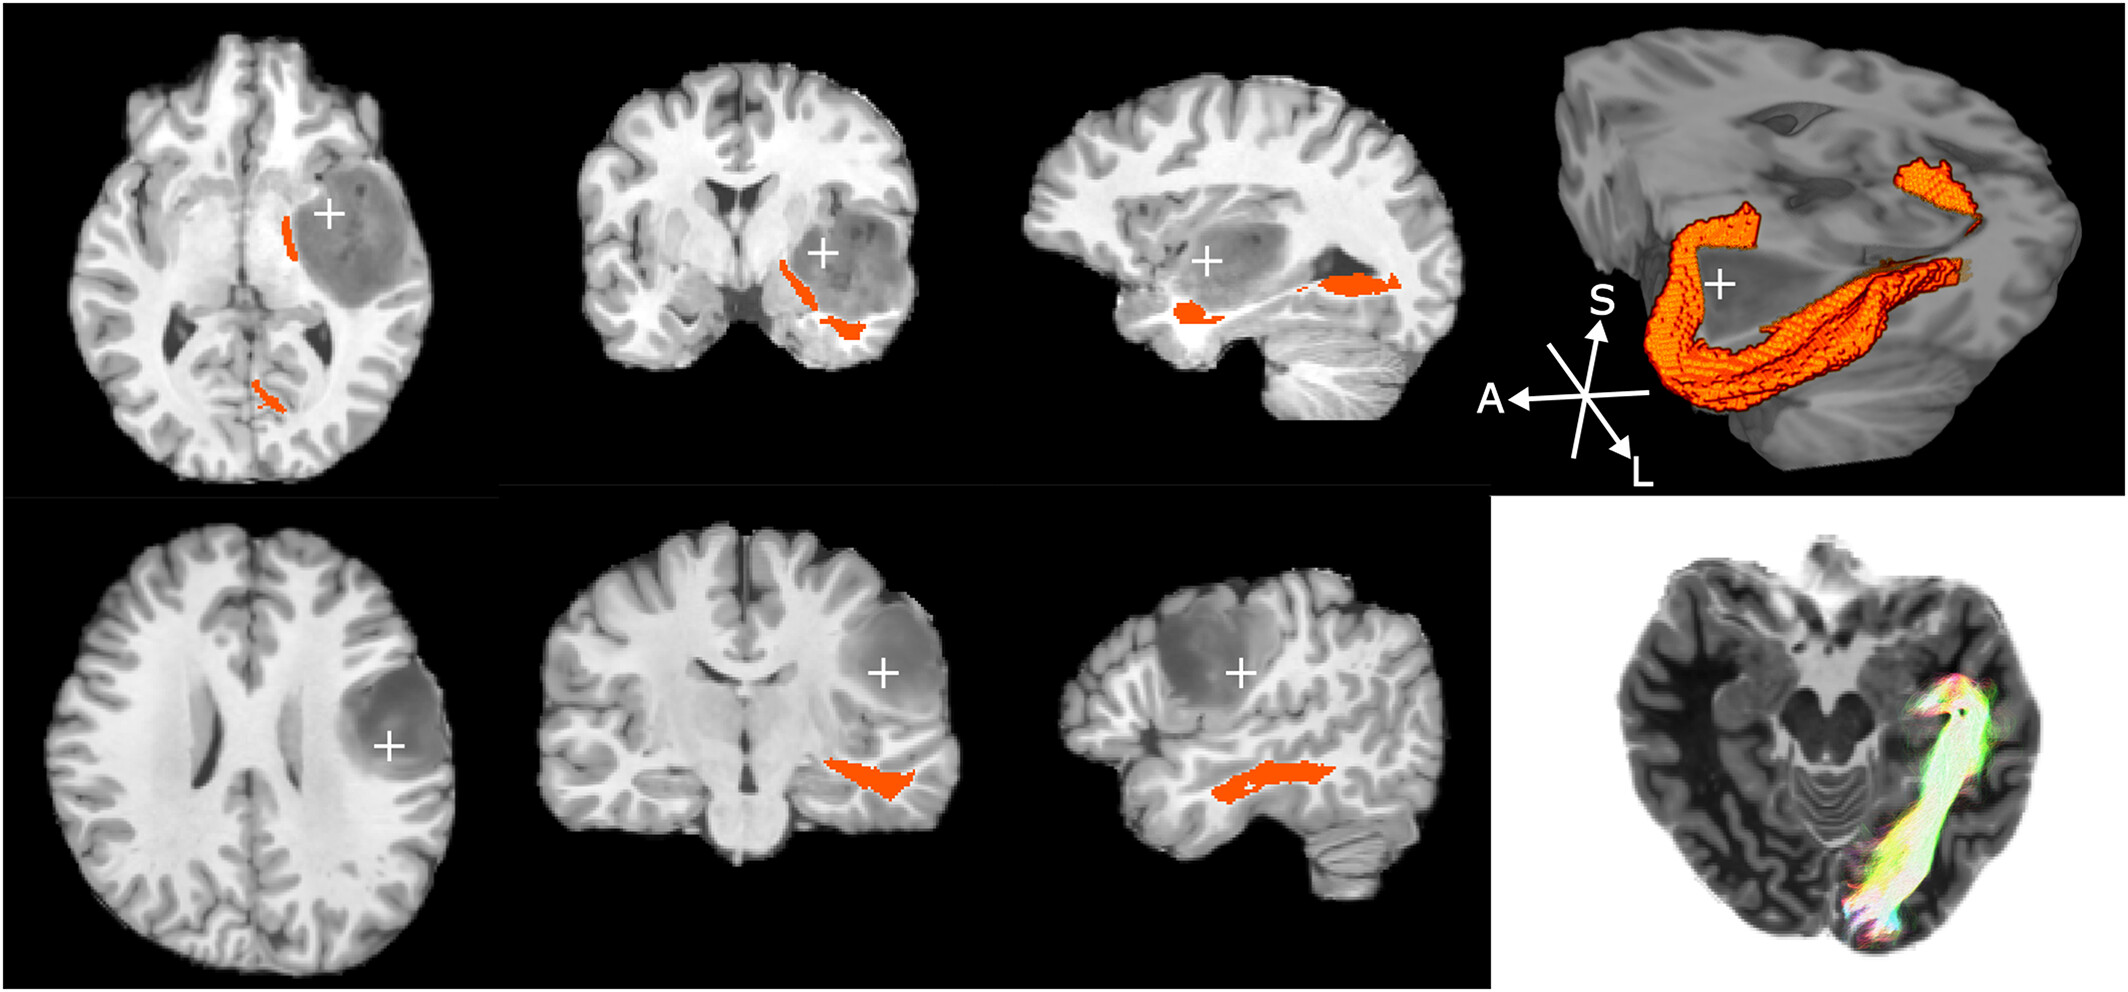

Not a traditional profile picture, I suppose. This is a quantitative map of my brain's connectivity.

I put together the MR sequence and data processing that generated this image to help surgeons plan safer brain surgery. Personalised maps like these are used to avoid causing paralysis, blindness, language deficits, and so on.

Fully automated delineation of the optic radiation for surgical planning using clinically feasible sequences

LB Reid, E Martínez-Heras, JV Manjón, RL Jeffree, H Alexander, et al. Human Brain Mapping